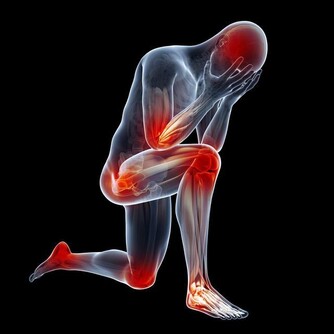

6. 運動時疼痛

如果輕輕一動就會感覺疼,那就是血栓的另一個早期預警信號。一個人從正常行為如彎腰、笑或咳嗽中感到不適,表明血栓有可能到達肺部,必須迅速治療。情況嚴重時,還要掛急診。7.原因不明的咳嗽